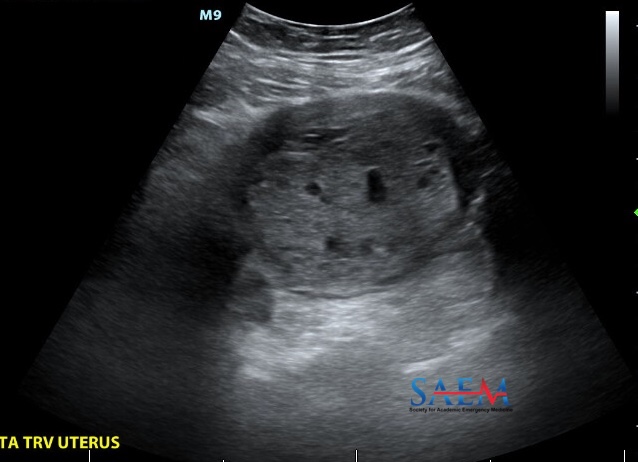

SAEM Clinical Images Series: Bilateral Leg Swelling with a Uterine Twist Why does this patient have shortness of breath? https://t.co/rPnGeGRonO

@SAEMonline

emDOCs Podcast – Episode 135: Ectopic Pregnancy Myths Part 1 by Brit Long #FOAMed #FOAMtox #FOAMus #FOAMped @EMhighAK @long_brit @MprizzleER

This podcast evaluates myths and misconceptions in ectopic pregnancy, focusing on risk factors, history, and exam.